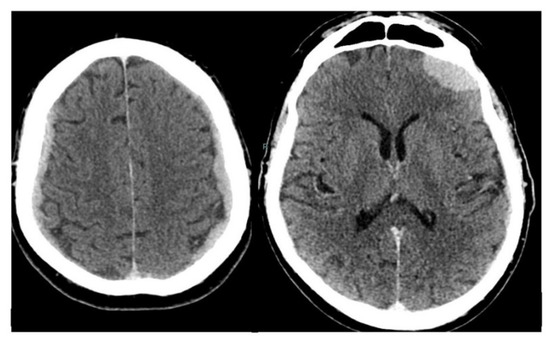

Figure 2. A brain contrast-enhanced computed tomography (CECT) scan was therefore performed and showed extensive pathologic iso-hyperdense tissue along the dura on both sides with intense and homogeneous enhancement following intravenous injection of the contrast medium. The dural-subdural pathologic tissue along the fronto-parietal convexities corresponded to the “en plaque” morphology discussed by Nzokou et al. [1] which may simulate sub-dural hematomas. In the weeks immediately following the CT scan, the patient’s clinical conditions rapidly worsened. He was treated with medical therapy with palliative intent. The patient died of arrhythmia approximately one month after the CT. Intracranial prostate cancer metastases are rare with an estimated range varying from 0.6% to 4.4% of cases [2]. In an extensive review of 16,280 patients with prostate cancer, only 28 (0.001%) were found to have dural metastases [3], while an autoptic study on 559 patients with hematogenous metastatic diffusion showed meningeal involvement in 5.9% of cases [4]. Since recent drug trials show improved overall survival for castration-resistant prostate cancer, it seems likely that cases of previously unrecognized dural metastases may become more clinically relevant. Cases of dural and parenchimal metastases from prostate cancer have been reported in the literature [5,6,7,8,9], but data on dural metastases with a bilateral “en plaque” morphological pattern are more limited [1,10]. To the best of our knowledge, no reports on 18F-FCH appearance in dural metastases from prostate cancer are present in the English scientific literature. As previously stated, the CT appearance of the metastatic lesions along the cerebral convexities was similar to sub-dural hematomas, but the pathologic tissue showed intense enhancement and was hypermetabolic on 18F-FCH PET/CT in contrast to hemorrhagic collections. Due to the extensive bilateral metastatic dural-subdural tissue, the patient was not considered eligible for surgery or whole-brain irradiation and received palliative care. In the present case, the use of combined molecular and morphological imaging avoided invasive diagnostic procedures in a patient with a dismal prognosis. The incidence of this unusual metastatic localization may be increasing as therapies for systemic cancer improve and patients survive longer.